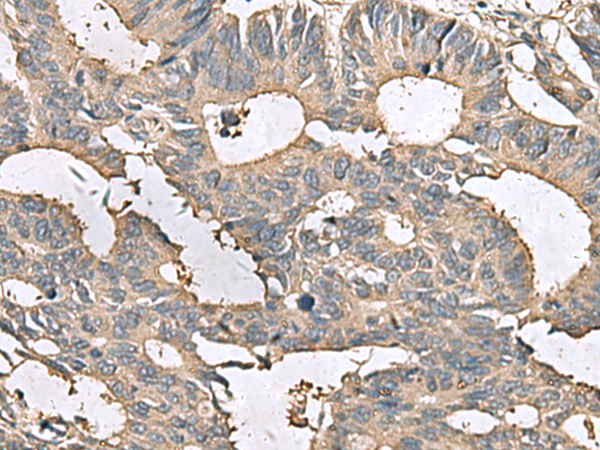

IHC positive control: |

Human cervical cancer and Human colorectal cancer |

IHC Recommend dilution: |

50-200 |